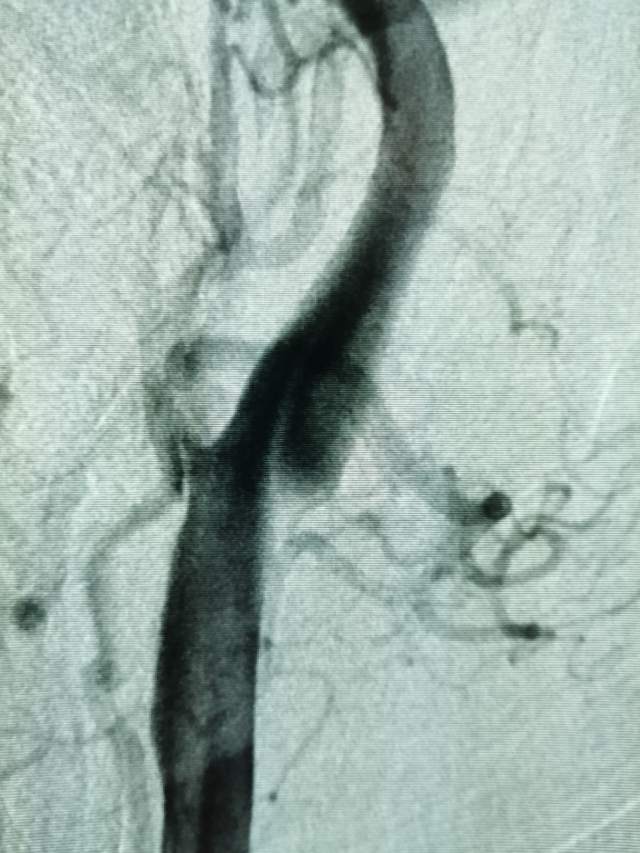

进一步行DSA检查后发现:左侧颈内动脉起始部有一个颈动脉蹼。这个血管内的“蹼”,是一个薄片状的结构,类似掌部的“蹼”,它会在颈内动脉起始部产生“扰流效应”,瘀滞的血流存在栓子形成和脱落的风险………,冲散的栓子可以“天女散花”,也可以“天上掉下石头”,这不,这位兄弟就被掉下的石头砸到颅内的功能区了,手脚语言都砸坏了。

向家属讲明来龙去脉之后,家属和患者本人积极寻求进一步的治疗。于是限期给予病变简单外科干预,消除了潜在的风险,远端的有效血流也相对增加了(有利于功能恢复),再也不用担心“天上”掉石头下来砸着“脑袋”了。